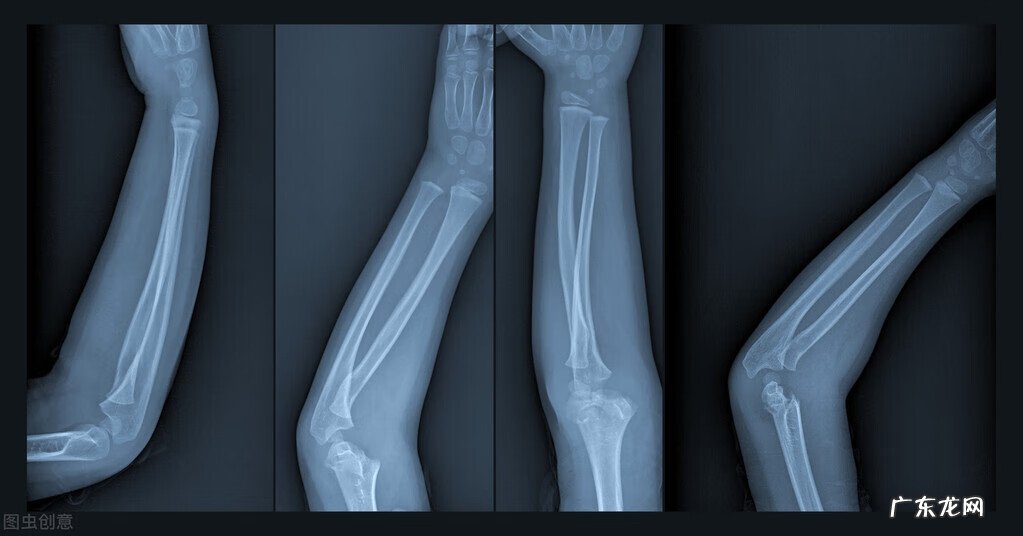

【骨折了吃什么好的最快 骨折吃什么好的比较快】骨折了可以多吃一些富含高蛋白的食物 , 有利于骨头愈合 。

一般情况下骨折是可以愈合的 , 骨折严重程度不同 , 恢复所需时间也不同 。一般情况下骨折修复的组织反应在24小时以内就会出现 , 所以骨折以后应尽早进行复位 , 争取在2~3小时内就进行 。